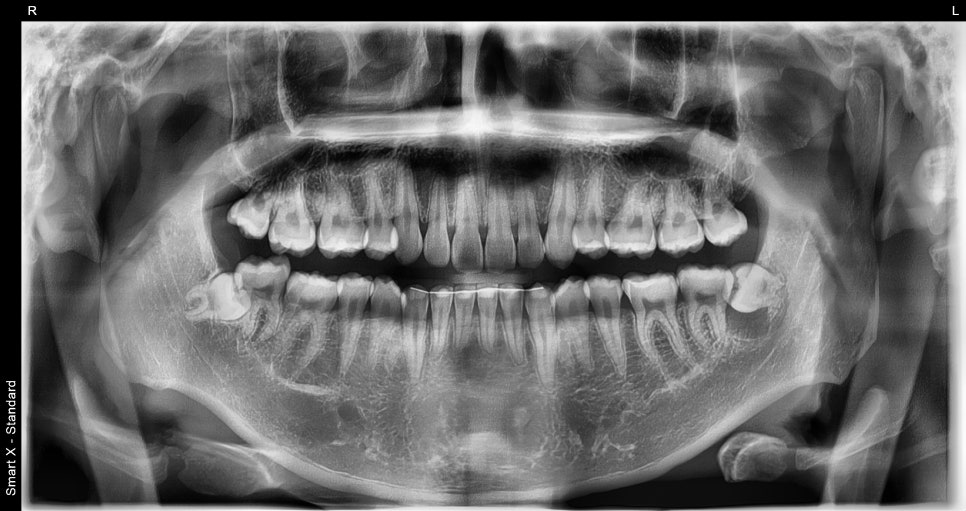

Initial X-ray at the time of the visit

A patient in their 20s visited after repeatedly experiencing swelling and subsiding of the gum around the lower left molar area.

As a result of panoramic and small X-ray imaging,

an over 6 mm radiolucent lesion (dark-appearing cystic tissue) beneath the left mandibular third molar was identified,

and a tooth cyst was suspected.

Since the tooth was in a condition where it could be saved without extraction,

a plan was made for cyst removal surgery along with extraction of the impacted wisdom tooth.